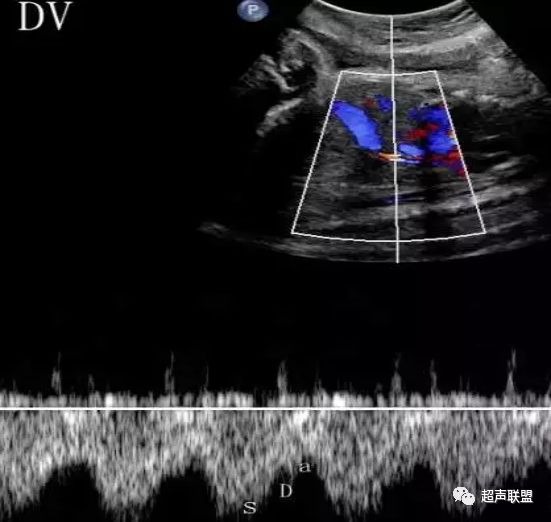

图5 胎儿宫内正常静脉导管

图6 胎儿宫内缺氧时静脉导管a波反向

图7 正常中孕期子宫动脉频谱